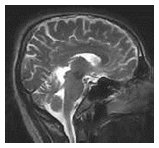

• NMR – Nuclear Magnetic Resonance – Scanning • Brain wave activity – brain tumour , defective cells • Separate damaged cells and healthy cells • Superconducting solenoids – magneto hydrodynamic power generation – plasma maintenance |

![]() |